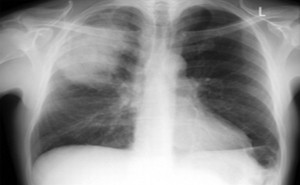

Idiopathic pulmonary fibrosis (IPF) is a chronic, progressive, fibroinflammatory lung disease associated with increased morbidity and mortality. As its name suggests, the exact cause of the disease is not known. However, some genetic and environmental factors have been observed concurrently with the condition and are considered potential etiolo...

Annals of the American Thoracic Society: Published on October, 2022Chronic obstructive pulmonary disease (COPD) is a leading cause of death worldwide [1, 2]. COPD exacerbations that are related to poor prognosis and severe COPD exacerbations requiring hospital admission.Beta-adrenoceptor (β-ADR) antagonists, or “beta blockers,” are indicated for...

JAMA Pediatrics: Published on November 2022A Systematic Review and Meta-analysisTAKE-HOME MESSAGEAre shorter courses of antibiotics as good as longer courses?This systematic review and meta-analysis assessed whether shorter courses of antibiotics are noninferior to longer courses of antibiotics for nonsevere community-acquired pneumonia (CAP) in...

The rapidly escalating coronavirus disease 2019 (COVID-19) pandemic has focused attention on the diagnosis and treatment of patients with acute respiratory infection in an unprecedented manner. Although most of the lung injury patients have is believed to be caused by the virus, concern over bacterial co-infection also informs current treatmen...

Antibiotics treatment for bacterial pneumonia in adults in hospital  Antibiotic management of suspected or confirmed bacterial pneumonia in adults in hospital during the COVID-19 pandemic. This includes people presenting to hospital with moderate to severe community-acquired pneumonia and people who develop pneumonia while in hospital.COVID...